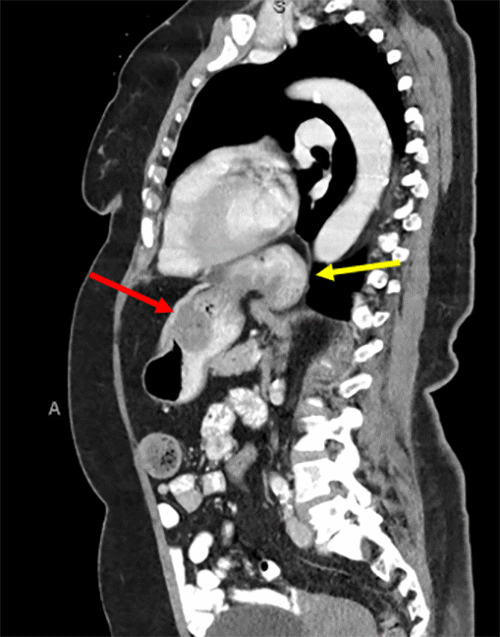

Figure 2: Abdominal CT Scan. Published with Permission

Note evidence of tumor growth on anterior wall of the stomach (red arrow); CT also displays sliding hiatal hernia (yellow arrow)

The patient was subsequently referred to a general surgeon to address the tumor and hiatal hernia. The CT was reviewed, and a subsequent upper GI swallow study (Figure 4) was ordered. The UGI swallow study was conducted to evaluate the esophagogastric anatomy and functionality. The patient was determined to be a good surgical candidate for a robotic gastric wedge resection. Additionally, a hiatal hernia repair was planned to occur at the time of the tumor removal. There would be no neoadjuvant therapy ahead of the procedure.